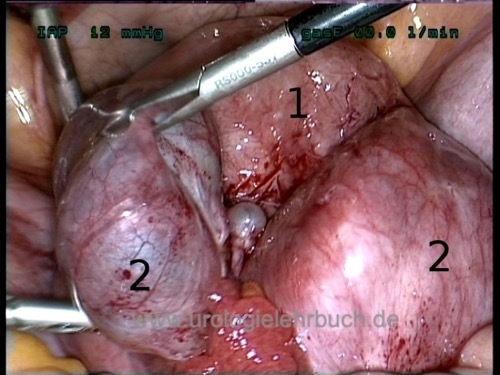

Laparoskopie:

Die Laparoskopie ist die Methode der Wahl zur Diagnose der Endometriosis genitalis externa: histologische Sicherung und Therapie. Bei Infertilität kann die Laparoskopie mit der Hysteroskopie und Chromopertubation kombiniert werden.

Laparoskopische Destruktion aller erreichbaren Endometrioseherde mit Laser, Exzision oder Koagulation. Ovarialendometriome werden inklusive Zystenbalg reseziert. Randomisierte Studien bestätigten die Effektivität der laparoskopischen Therapie (vs. diagnostische Laparoskopie).